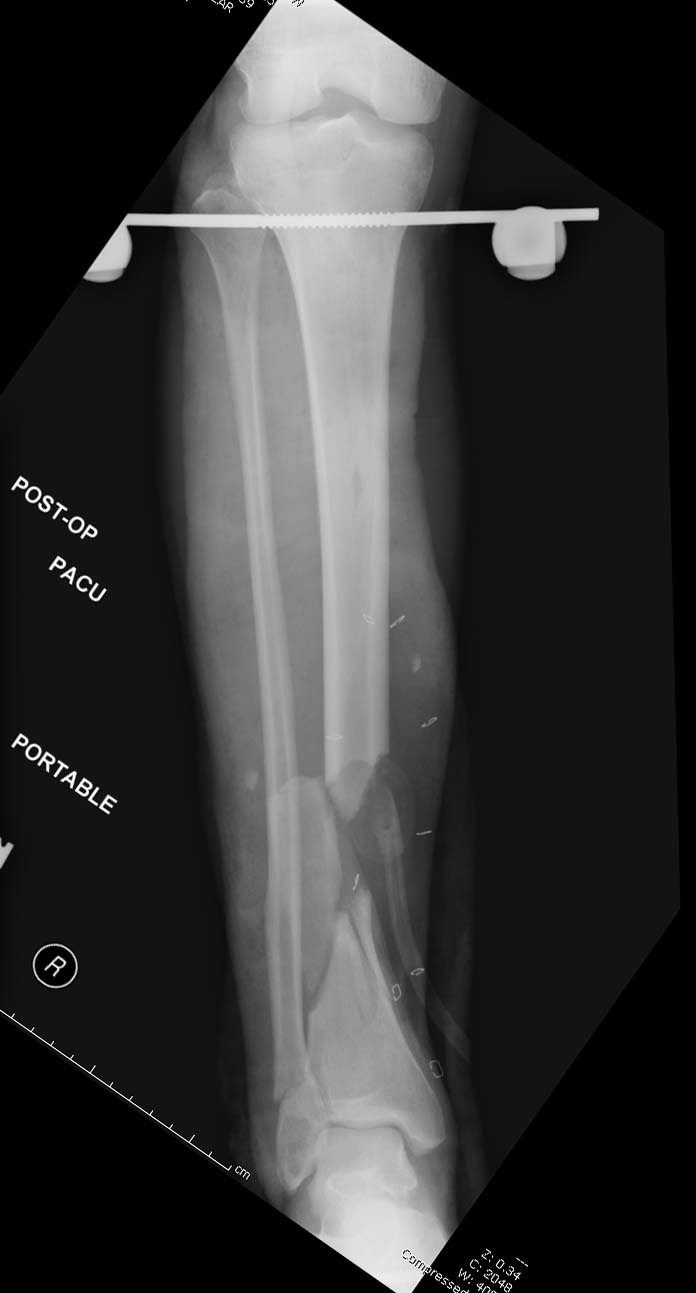

Данный случай не огнестрельная рана, а результат мотоциклетной аварии. Независимо от повреждения при таких обширных дефектах мягких и костной тканей применяется схожая тактика. Как видно, после нескольких I&D для создания “pseudo membrane” применили цилиндрический блок из цемента. Дефект мягких тканей закрыли свободным Anterior Thigh Graft. Из малого доступа цилиндр удален небольшими кусочками, а пространство заполнили бусами для освобождения пространства. По мере приближения регенерата освободили пространство удалением бус через небольшой разрез. Этап созревание регенерата можно было ускорить усилением интрамедуллярным гвоздем, но решили закончить методом Илизарова.

Из истории Афганской войны известно, что "доктрина убирать все фрагменты с последующим замещением дефекта" привела к долгим восстановительным операциям. А проведенные работы в США в начале 90х по фиксации огнестрельных переломов показали, что классические методы фиксации гвоздем намного лучше, чем сложные восстановительные операции. Чем быстрее создается стабильность, тем лучше, и при сохранении длины костей переломы срастаются в те же сроки и с очень низким процентом осложнений.